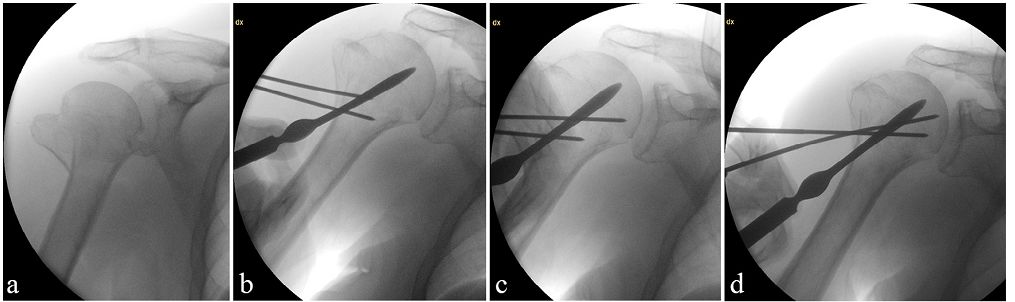

C臂机透视,螺纹针撬拨复位后,植入一组螺纹针固定。

置入另外2-3组螺纹针进一步巩固复位。